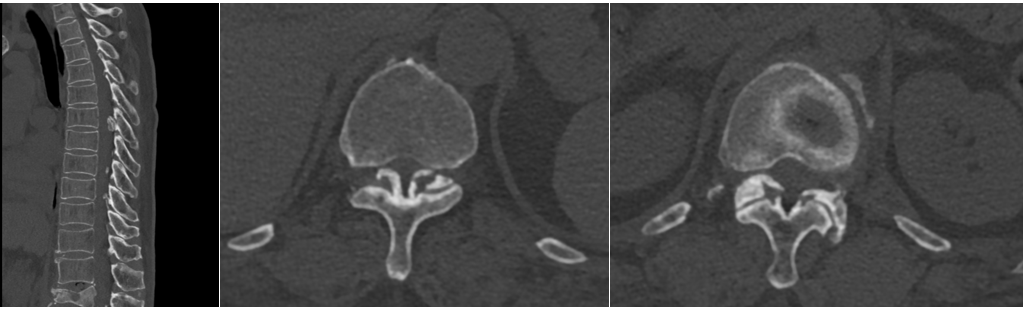

王阿姨近几年来时常感觉双下肢麻木,行走不稳,容易跌倒。王阿姨最近一次摔倒后,出现腰部剧痛、双下肢无力、行走困难的症状,家属立即带着王阿姨来到独墅湖医院骨科姜为民主任诊室就医。经查CT及MR显示:患者 L1压缩性骨折,T5-T12后纵韧带骨化。

胸椎管狭窄黄韧带骨化症是一类高致残性疾病,薄薄的神经如同松软的豆腐,任何一点损伤都可能导致不可逆的后果,切除骨化的黄韧带就好比在刀尖上表演舞蹈。姜主任将最新的UBE技术应用到王阿姨的手术治疗中,通过3个1cm的小切口在内镜下顺利从胸椎后方对T5-T7椎板完成了切除减压,并通过薄化技术一点一点切除骨化的黄韧带,用时153分钟顺利完成了“内镜下胸椎椎板切除减压术+黄韧带切除术”,术中出血60ml。术后,患者下肢麻木症状明显好转。在医院稍作休养后,即顺利康复出院。这次的UBE微创手术让王阿姨的印象尤为深刻,切实体会到了微创手术的神奇。

胸椎管狭窄症是指先天性或后天退变因素等导致的胸椎管横断面积缩小,脊髓受压而产生的一系列症候群。胸椎管狭窄症常引起严重的脊髓损害,导致下肢瘫痪等严重后果。后天性胸椎管狭窄症最常见的病因是胸椎黄韧带骨化。